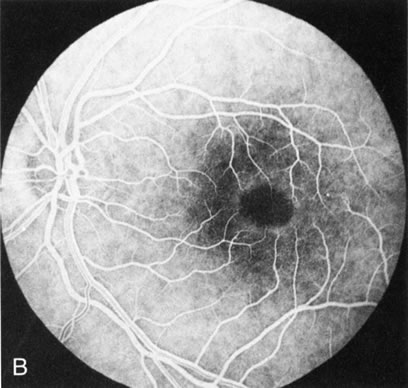

Fig. 1. Retinitis pigmentosa. A. A typical area of bone spicule pigmentation. B. Diffuse dye leakage is apparent throughout the posterior pole. C. The early angiogram shows dilated and irregular retinal radial peripapillary capillaries and perifoveal retinal capillaries. D. Leakage from these vessels are evident in the late angiogram.

Dye leakage in RP may occur from the retinal vessels or at the level of the retinal pigment epithelium (Fig. 1B).2–4 The leakage may be seen in the macula and posterior pole, along the vascular arcades in the distribution of the radial peripapillary capillaries, and in the periphery (where an exudative vasculopathy resembling Coats' disease is suggested).

Of more clinical importance is the role of FA in the diagnosis and treatment of cystoid macular edema (CME) (Fig. 1C and D). Stereoscopic FA indicates that the leakage, which may be diffuse or have the typical petaloid stellate appearance of CME, can come from the perifoveal retinal capillaries, from the choroid through the RPE, or from a combination of both sources.4 With the recent suggestion that CME in RP may be successfully treated with acetazolamide,5, 6 FA is thus important to document the diagnosis of CME, establish the origin(s) of leakage, and follow patients during and after therapy.